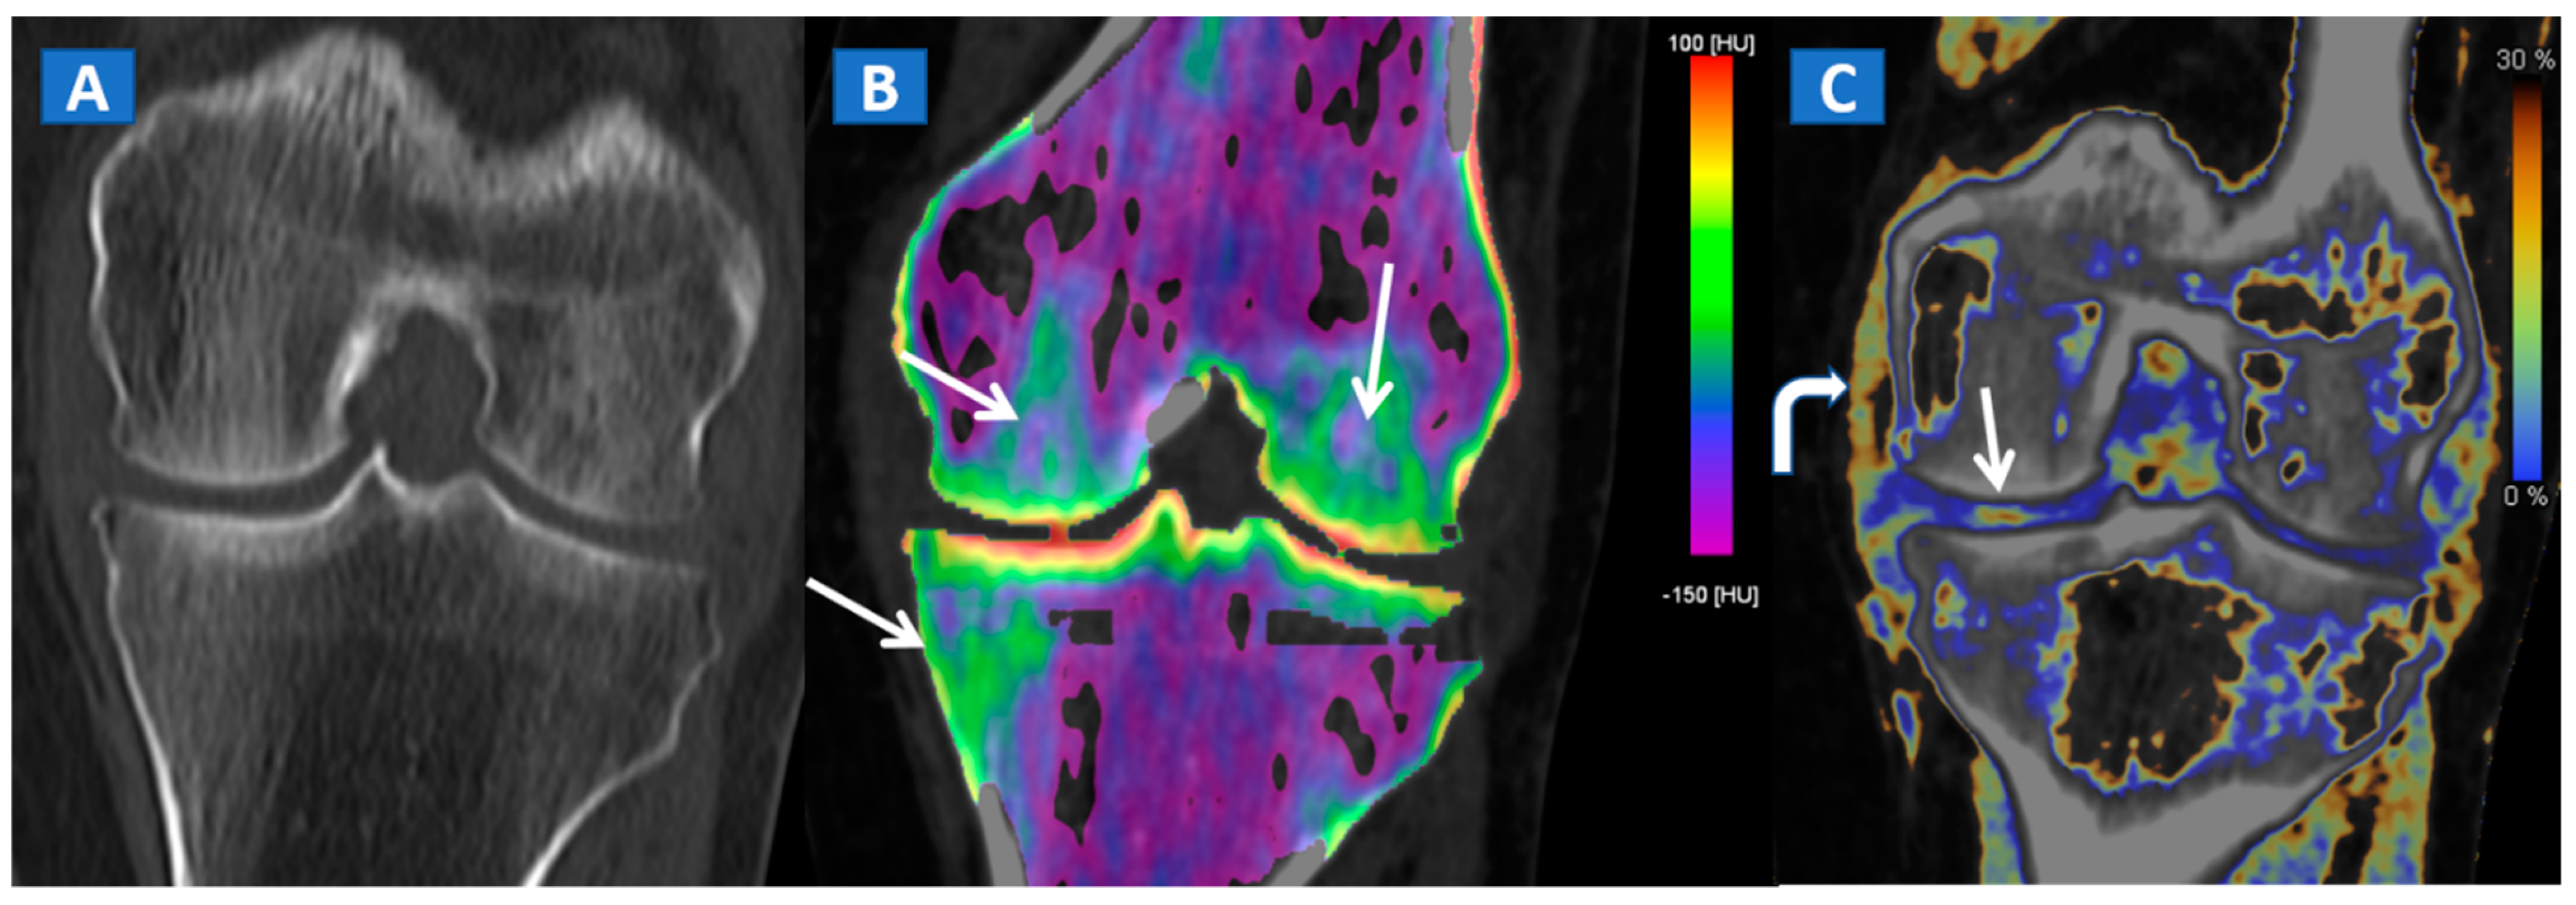

DECT can also accurately depict BME in post-traumatic fractures of the knee (Figure 5). Specifically, DECT can identify BME associated with ligamentous injuries following indirect trauma [6,15]. Moreover, additional color-coding can be used to better delineate meniscal tears (Figure 6). OCL, of the knee or ankle, are usually apparent from a markedly oedematous subchondral region (such as femoral condyle or astragalic dome), surrounded by a more subtle BME (Figure 7). With the availability of isotropic high-resolution CT images, it is possible to rule out migrated fragments and to confirm the integrity of the cortical bone.

Figure 7.

A 44-year-old male with post-traumatic OCL of the talar dome. On the coronal STIR MRI image (A), a hyperintense subchondral area of BME is depicted on the medial aspect of the talar dome (arrow), which is consistent with the diagnosis of OCL of the talus. The lesion appears hypointense on the T1-weighted images ((B); arrow). On the 1 mm reconstructed 2D coronal DECT image (C) and coronal 3D DECT map, the lesion appears as a subchondral oedematous area (arrow), due to its increased water content. On the corresponding 3D image (D) the BME is coded in green (arrow).

Typically, the talus is the site most often involved in post-traumatic BME of the ankle. Subchondral bone sclerosis and thick cortical bone in the midfoot area may present significant limitations here [16].